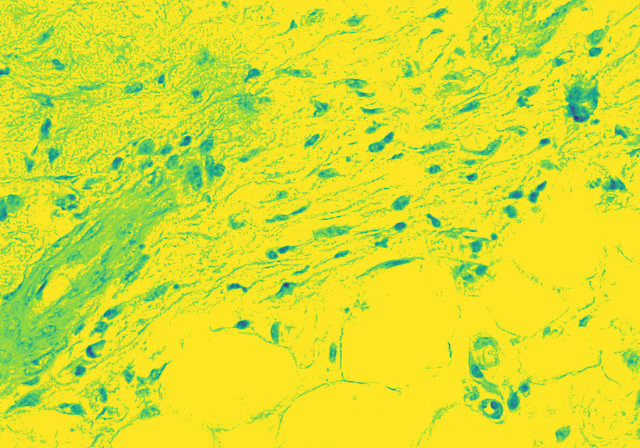

Histopathological Image Analysis of White Blood Cells

Sample Images

The project is to identify and count the White Blood Cells in a Skin Tissue. Firstly, we have to differentiate between RBCs, WBCs and Platelets. Not only that, we have to take into account, the presence of hair follicle in the skin sample. Then, WBCs have been identified, we have to further classify WBCs into their aforementioned types. The classification will be done on the basis of the number of nucleus in the types of WBCs. Lastly, the count can be categorized as to be within, above or below the normal count of 4,500 to 11,000 microliter. Thus, identifying whether or not the sample is infected or not.

Our new approach will be to dive into Fully Convolutional Neural Networks for the task of “Semantic Image Segmentation”. Semantic Image Segmentation is the task of segmenting an image and coloring the segmented parts with the color of the classification class. We will adopt the technique on biological data and first make a CNN to segment our image and then move forward with the semantic analysis task. Making it a 2 way process will help us deal with the difficulties step by step. This novel approach of segmenting on cell level with CNN is an experiment that may give unlikely result. We are exploring various other techniques side by side since the task is tedious and accuracy is highly important.